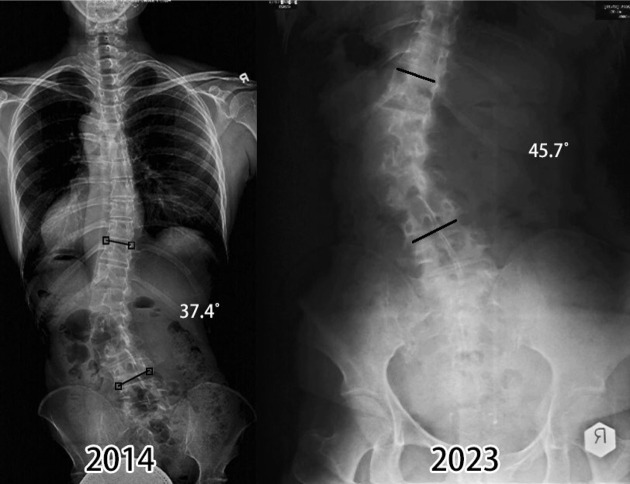

【目的】本研究探讨绝经后胸腰椎弯曲妇女进行脊柱侧凸特异性锻炼是否与脊柱弯曲稳定有关。【病例描述】我们描述了三名绝经后胸腰椎侧凸的妇女进行了大约十年的脊柱侧凸专项锻炼的结果。病例1骨密度正常,胸腰椎侧凸超过64°,每天在家坚持锻炼半小时。病例2和病例3骨质减少,胸腰椎弯曲度分别为64°和45°。他们在八年的时间里很少做这些练习,特别是在新冠肺炎爆发的三年里,他们停止了这些练习。[结果]三个案例的结果不同。病例1效果最好,胸腰椎弯曲稳定,无疼痛。病例2和病例3有弯曲性进展,疼痛轻微,需要偶尔使用止痛药。【讨论】我们的研究结果表明,定期的脊柱侧凸专项锻炼、良好的骨矿物质密度和脊柱侧凸稳定之间存在潜在的关系。需要更多的研究来进一步了解运动、骨骼健康和脊柱侧凸进展之间的相互作用。

[Purpose] The study investigates whether performing scoliosis-specific exercises is related to curve stabilization in postmenopausal women with a thoracolumbar curve. [Case Description] We describe the outcome of three postmenopausal women with thoracolumbar scoliosis performing scoliosis-specific exercises for around ten years. Case 1 had a normal bone mineral density and thoracolumbar scoliosis over 64° and consistently performed the exercises at home for half an hour daily. Cases 2 and 3 had osteopenia and thoracolumbar curves of 64° and 45°, respectively. They did the exercises sparingly over eight years, particularly during the three years of COVID-19, when they stopped doing the exercises. [Outcome] The outcomes of the three cases differ. Case 1 had the best result, with the thoracolumbar curve stabilized and no pain. Cases 2 and 3 had curve progression and had mild pain, requiring occasional pain medication. [Discussion] Our findings suggest a potential relationship between regular scoliosis-specific exercises, good bone mineral density, and scoliosis stabilization. More research is needed to further our understanding of the interplay between exercise, bone health, and scoliosis progression.